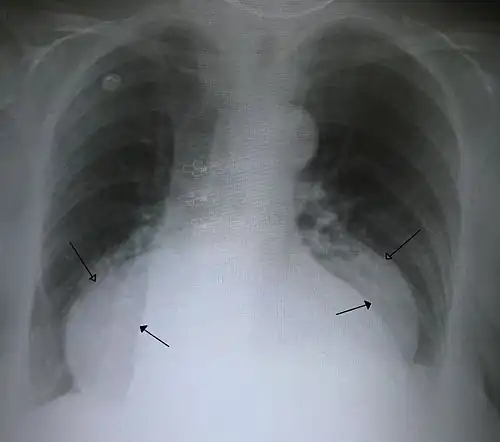

This hiatal hernia is mainly identified by an air-fluid level (labeled with arrows). -